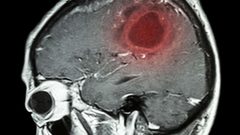

مصابون بسرطان الدماغ يكشفون أعراضا لم يعيروها سابقا أي أهمية

أعراض أولية لسرطان المخ على لسان مصابين بهذا المرض الخبيث